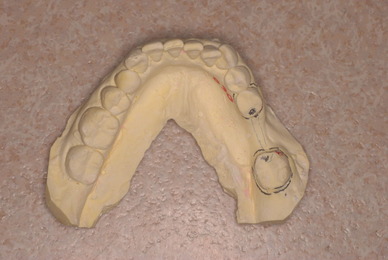

歯をいじられ体も心もボロボロになった患者さんからの手紙です。マスコミや権威などがいかにいい加減かわかります。歯は触らないほうがよろしいのです。

そもそも歯を触り何らかの金属やセラミックを入れる行為そのものが医学的には傷害処置ですから、なるべく避けるべき物なのです。

お口の中から差し歯、入れ歯、詰め物を追放しましょう!